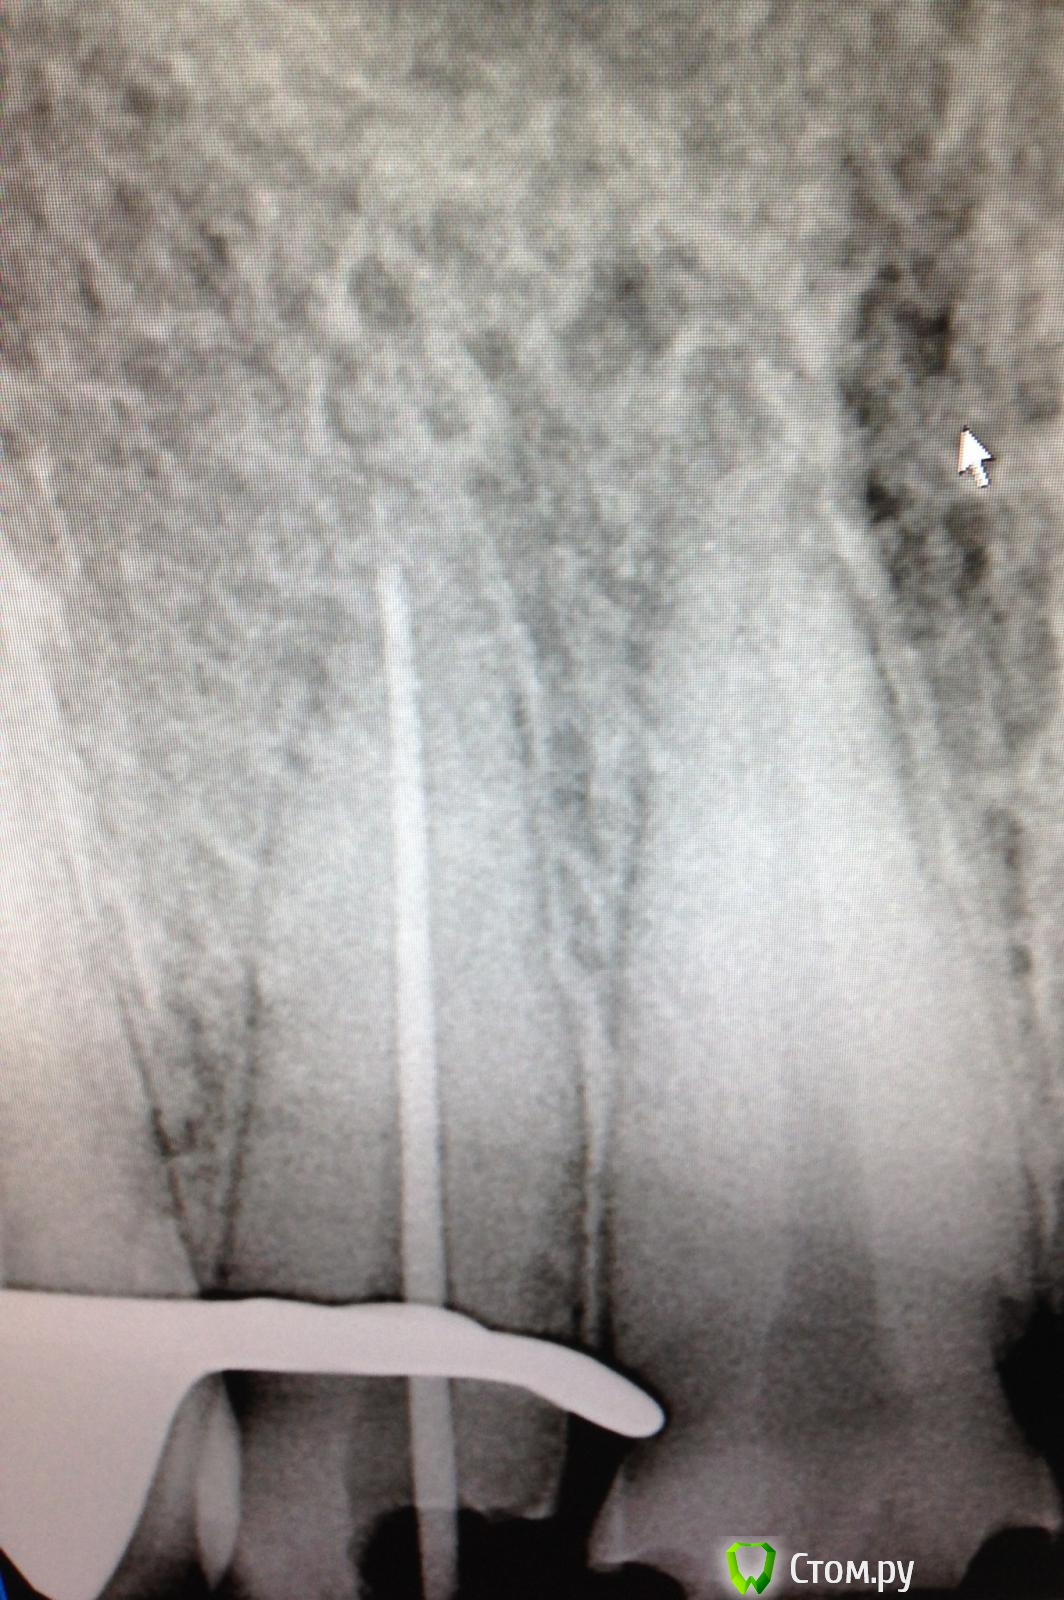

SSTi Опубликовано 19 сентября, 2014 Автор Поделиться Опубликовано 19 сентября, 2014 Новая кривулина. Начало. Попросил доктор знакомый полечить...)Неделю боли на накусывание. Иррадиируют в левый висок. Зуб 27. Внешне все ок. Маааленькая точечка в фиссуре. Шестерки нет. Делаю снимокТааааак. Позвонил доктору, сказал , как я счастлив, и приступил. Преп. Коффер. Дистально на уровне десны. Небный дистальный бугор ушел. В полости небольшой склероз. Мб сразу прошелся. Вообще без проблем. Только при хрусте файлов я чуть вспотел в области крестца))) расширились до 30.04 и дальше ручками 35.02. Мб 2 пока не нашел. Сулькус раскрыл - но там глухо. Поищем в следующий раз. Дистальный сначала только до уровня , как на снимке, потом прошел. Тоже 30.04 и 35.02. Небный- последние 3-4 мм дались с трудом. Но прошли. До 35.04 и 40.02. Мылись, сушились, кальцифицировались. Времянка. Продолжение следует 3 Ссылка на комментарий